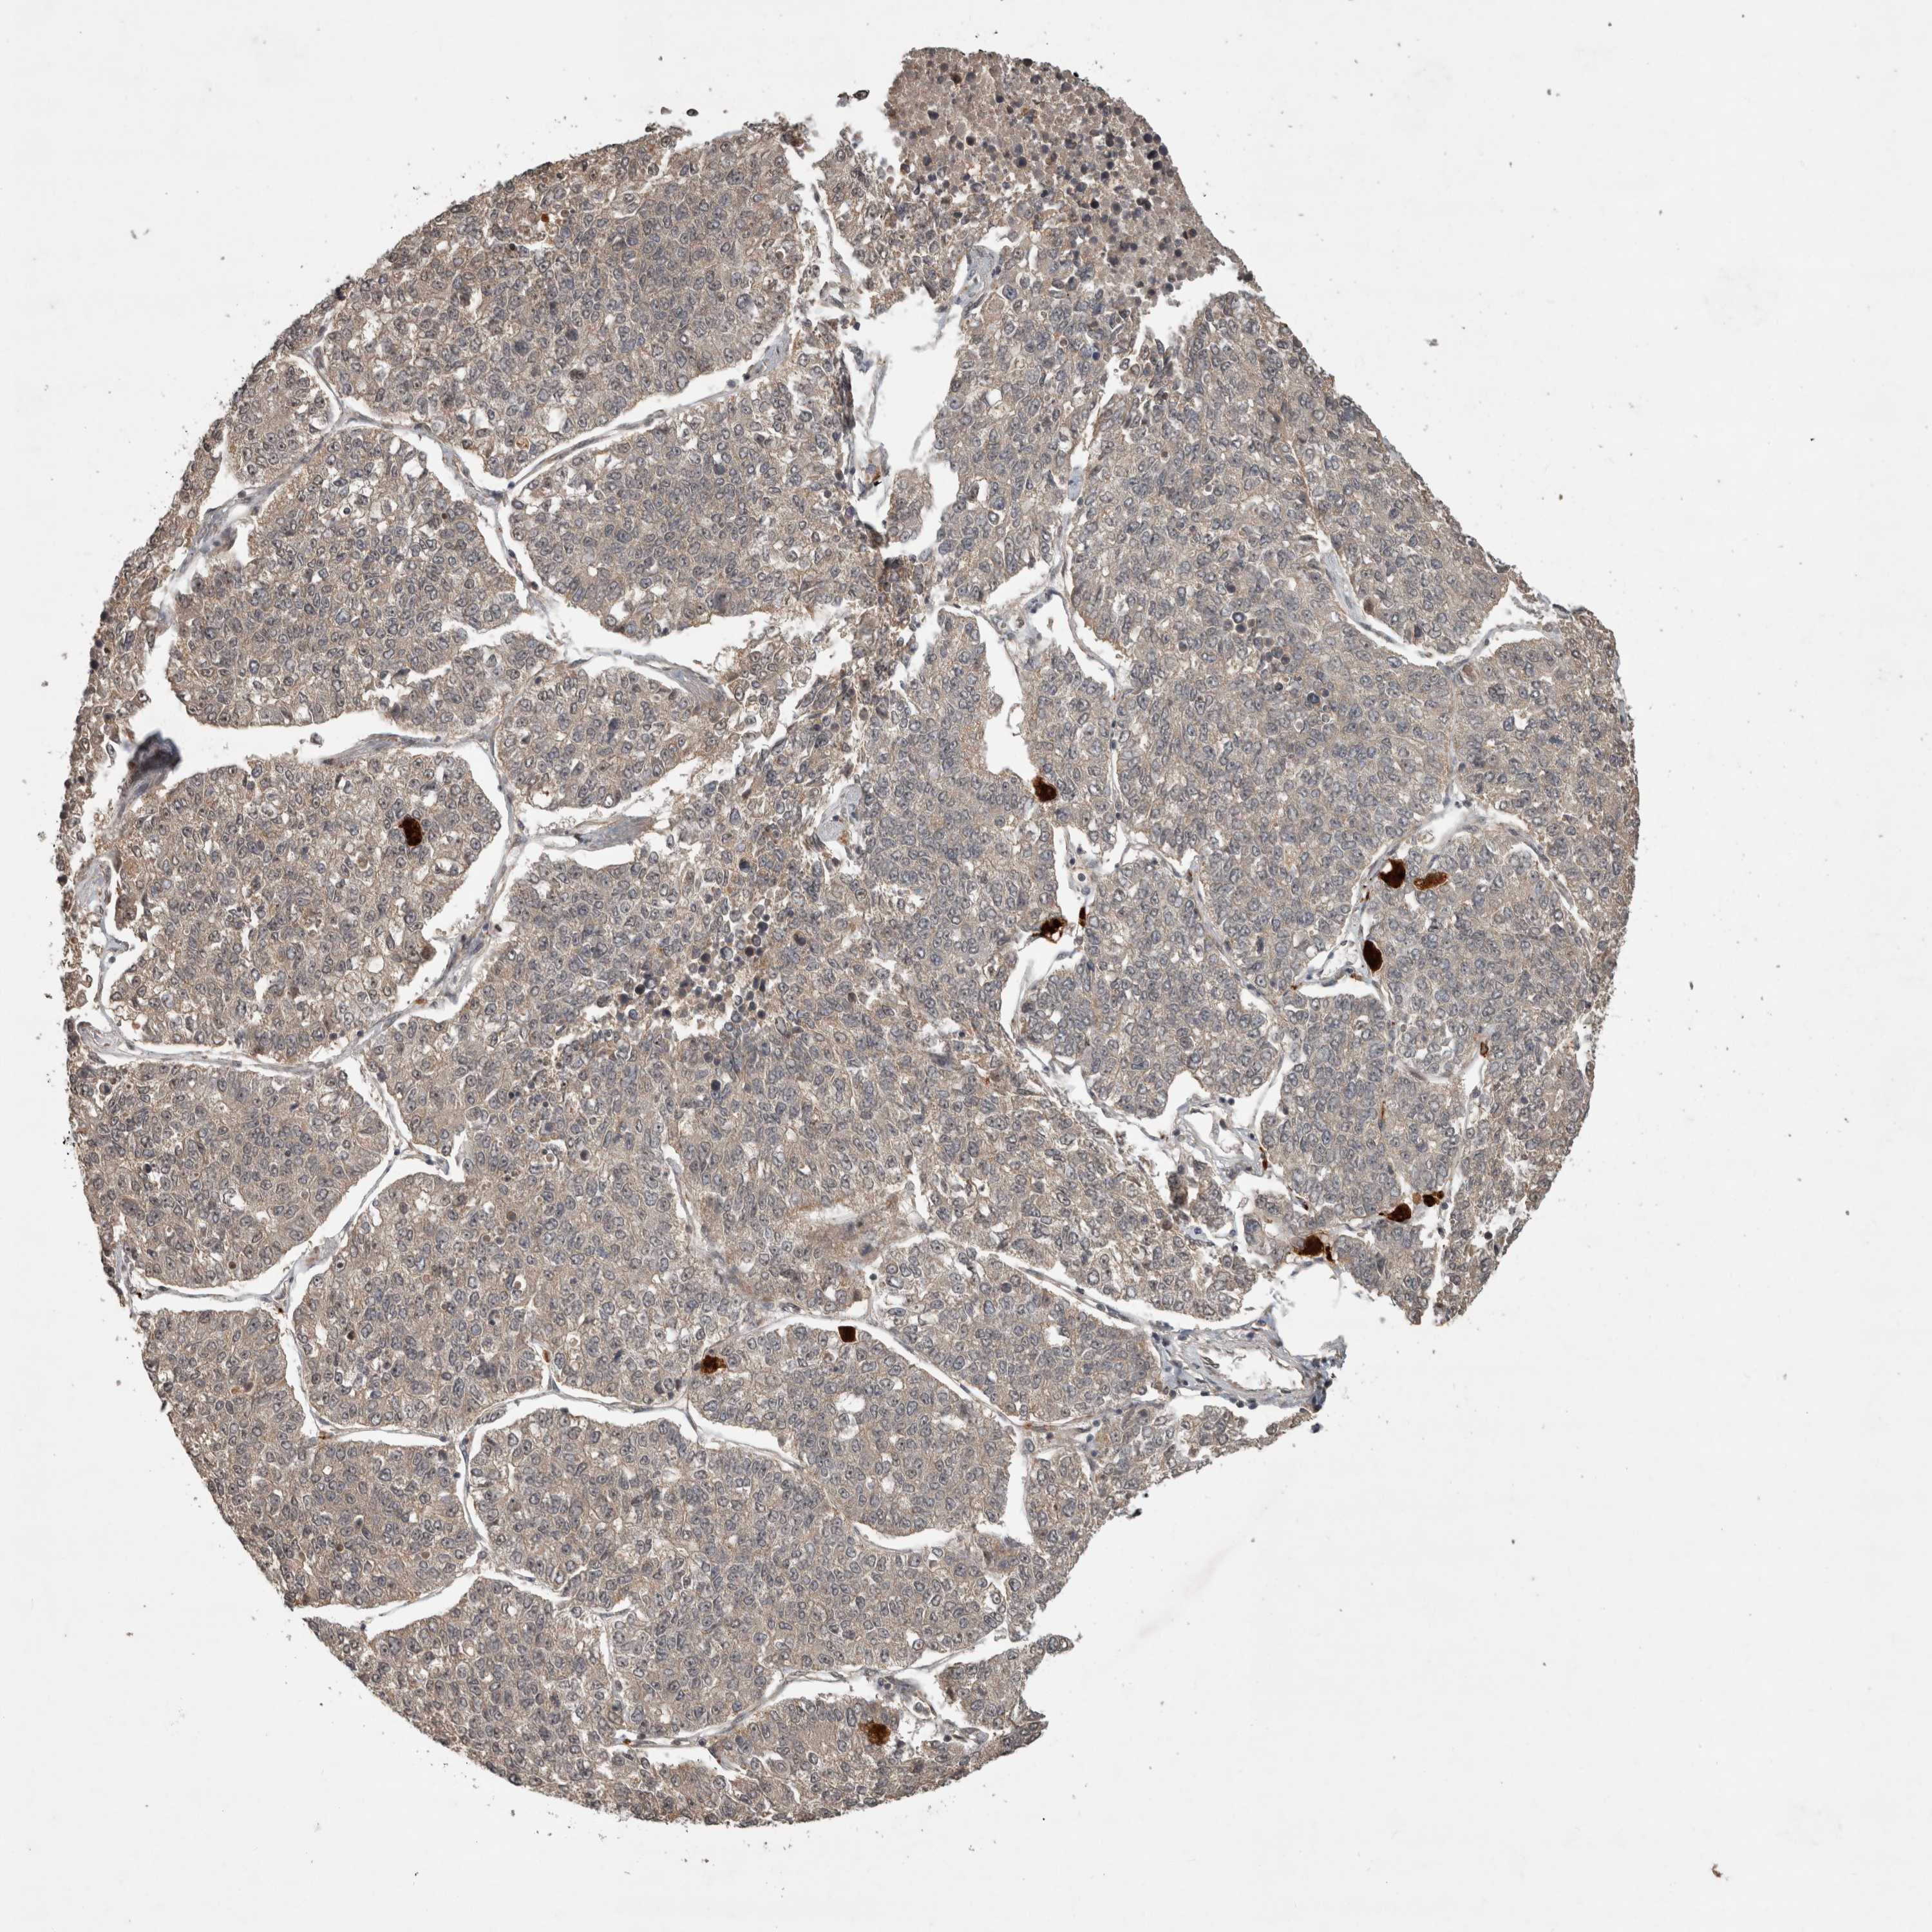

LUNG SQUAMOUS CELL CARCINOMA (TCGA) - Interactive survival scatter ploti

The Survival Scatter plot shows the clinical status (i.e. dead or alive) for all individuals in the patient cohort, based on the same data that underlies the corresponding Kaplan-Meier plots. Patients that are alive at last time for follow-up are shown in blue and patients who have died during the study are shown in red.

The x-axis shows the expression levels (FPKM) of the investigated gene in the tumor tissue at the time of diagnosis. The y-axis shows the follow-up time after diagnosis (years). Both axes are complimented with kernel density curves demonstrating the data density over the axes. The top density plot shows the expression levels (FPKM) distribution among dead (red) and alive patients (blue). The right density plot shows the data density of the survived years of dead patients with high and low expression levels respectively, stratified using the cutoff indicated by the vertical dashed line through the Survival Scatter plot. This cutoff is automatically defined based on the FPKM cutoff that minimizes the p-score. The cutoff can be changed by dragging the vertical line or by entering a cutoff value in the square labeled "Current cut-off".

Under the Survival Scatter plot the p-score landscape (black curve; left axis) is shown together with dead median separation (red curve; right axis). Dead median separation is the difference in median mRNA expression between patients who have died with high and low expression, respectively. It is calculated as follows: median FPKM expression of dead patients with high expression - median FPKM expression of dead patients with low expression. This is intended to aid the user in visually exploring custom cutoffs and the associated p-scores and dead median separation.

Individual patient data is displayed and can be filtered by clicking on one or more of the category buttons on the top of the page. Categories describing expression level and patient information include: high, low, alive, dead, female, male and tumor stages. The scale of the x-axis can be toggled between linear and log-scale by clicking on the "x log" button. Mouse-over function shows TCGA ID, patient information and mRNA expression (FPKM) for each patient.

& Survival analysisi

Kaplan-Meier plots summarize results from analysis of correlation between mRNA expression level and patient survival. Patients were divided based on level of expression into one of the two groups "low" (under cut off) or "high" (over cut off). X-axis shows time for survival (years) and y-axis shows the probability of survival, where 1.0 corresponds to 100 percent.

PITPNC1 is not prognostic in Lung Squamous Cell Carcinoma (TCGA)

: 4.66

P scorei

N/A

Average pTPM 4.3

Number of samples 489